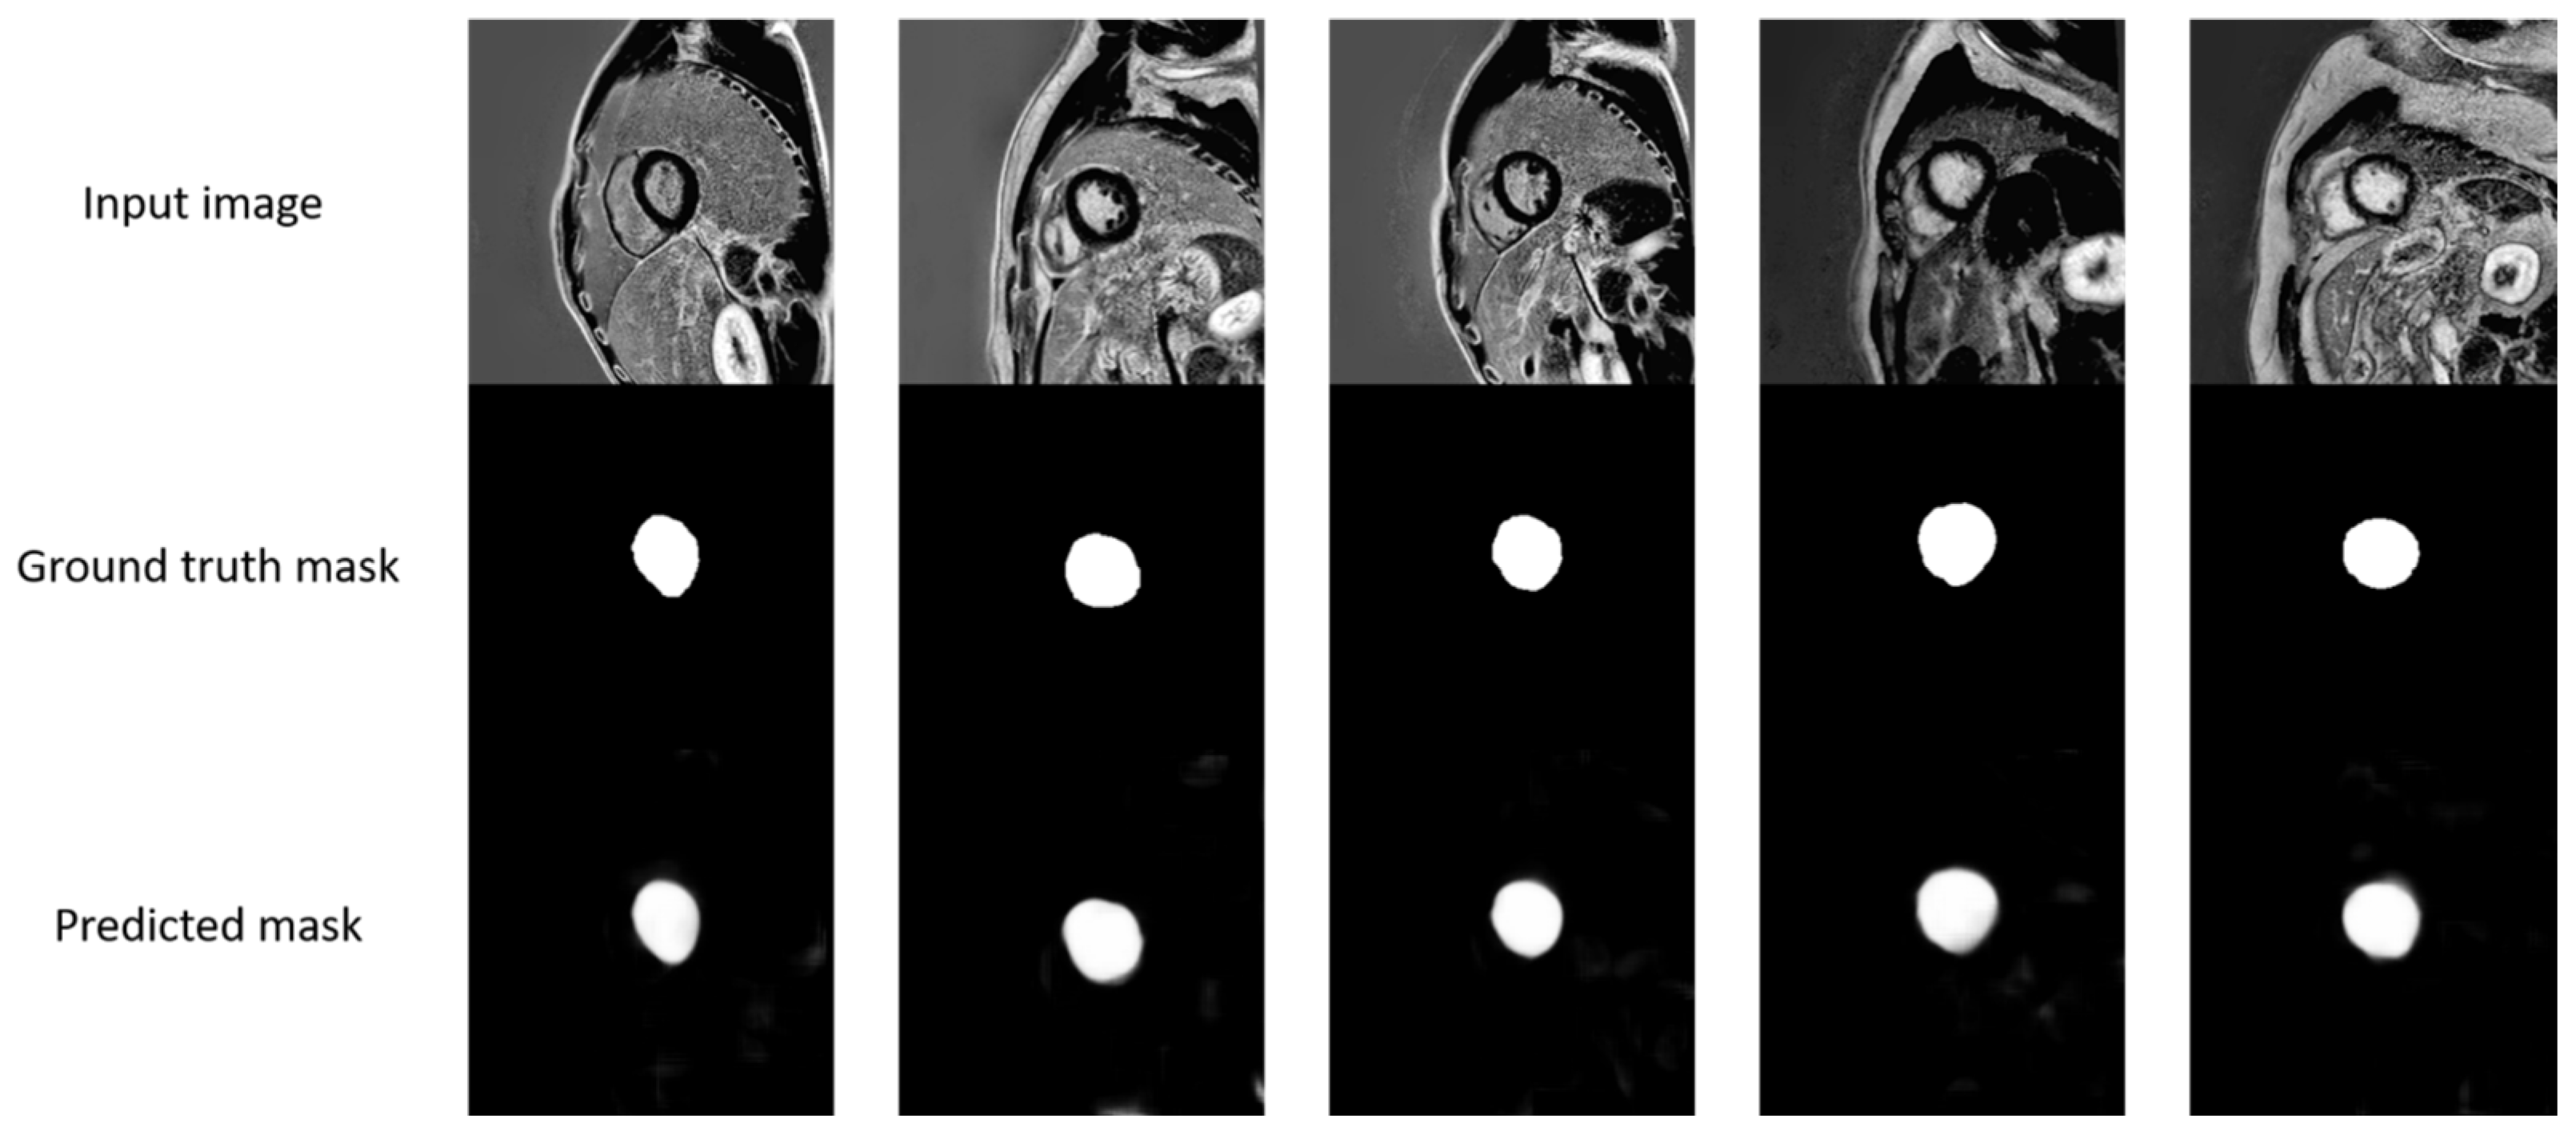

2.3.1. Extraction of the Region of Interest (ROI): Left Ventricle Segmentation

Concat-U-Net Segmentation

3.1. Left Ventricle Segmentation